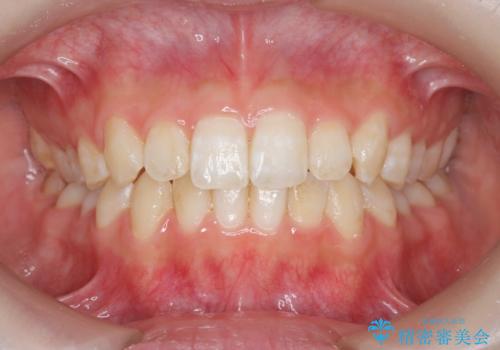

前歯のねじれを治したい マウスピース矯正治療

- 前歯のねじれを改善し、きれいな歯並びにしたい!と矯正治療を希望され来院されました。

マウスピース矯正システム、インビザラインのシミュレーションを用いて最終的な歯の位置をしっかりと確認したのち、きれいな歯並びとなるようマウスピース矯正治療を開始します。

ねじれとともに突き出たように見えていた前歯も見た目が大きく改善し、喜んでいただくことができました。